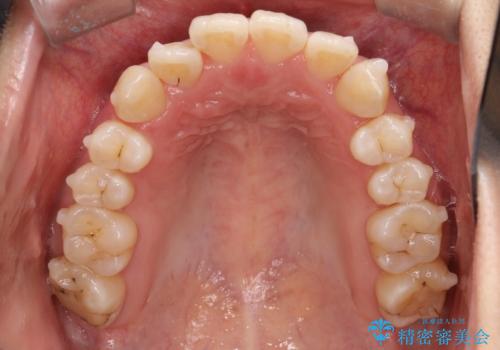

【インビザライン】前歯の凸凹をなおしたい

- 前歯の凸凹をなおしたいことを主訴にインビザラインにて矯正治療を行いました。

患者様にしっかりとインビザラインを使用して頂けたことで綺麗な仕上がりとなりました。